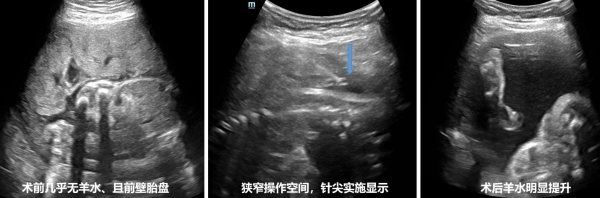

手术于8月8日上午顺利进行,在妇产科副主任段钊和超声科副主任姜珏的全程指导下,由余珊珊主任医师和何鑫主治医生为该患者实施超声引导下羊膜腔灌注手术中,术中团队面临以下主要技术难点:1、极窄的操作空间:患者的羊水量极少,前壁胎盘进一步限制了可供操作的空间。穿刺针只能在1cm宽的狭窄羊水间隙中操作,而该间隙因胎儿活动和孕妇呼吸而时有时无,稍有偏差就可能无法准确进入羊膜腔。这要求操作者在瞬息之间精准把握穿刺时机,操作过程中需要高超的手眼协调能力和丰富的临床经验。2、妊娠期子宫肌壁间血管异常丰富,增加了穿刺难度。穿刺针不仅要穿越厚实的肌壁,还需避开丰富血管丛,确保进入羊水间隙而不损伤血管。这对操作的精确性提出了极高的要求,稍有不慎可能导致严重出血或其他并发症。3、长时间、高精度操作要求:由于羊水灌注速度受限,每分钟仅能注入3ml,整个治疗过程持续了2小时。在此期间,医务人员需持续监控针尖位置,随时调整穿刺方向,避免因胎儿活动导致针头误伤胎儿或脱出羊膜腔。每一个微小的调整都必须准确无误,以确保灌注过程的顺利进行。4、MDT通力合作:妇产科团队对胎心和宫缩情况进行了密切监控、全操作期管理,确保母婴平安。

经过团队的精准操作和协同配合,操作顺利完成,当500毫升37℃温热的生理盐水进入羊膜腔内后,在超声监测下,清晰地看到胎儿从俯卧位改变为仰卧位,胎儿就像在碧蓝的海水中,终于可以自由的遨游。术后,羊水指数提升到了18CM。听到这个结果后。这位准妈妈开心的说:“医生,通过你们的努力,我的孩子终于自由了,谢谢你们。”